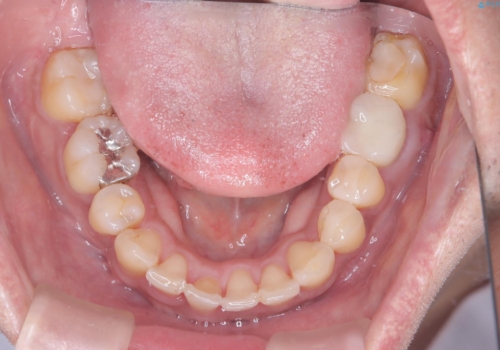

【ワイヤー矯正】八重歯と下の歯の凸凹を治したい

- 主訴:右上の八重歯と、下の歯の凸凹を治したい

上顎右側第一小臼歯と下顎右側第一小臼歯を抜歯しワイヤー矯正を行いました。

右側2級、左側1関係だったため、右側上下第一小臼歯を抜歯し、ワイヤー矯正を行いました。